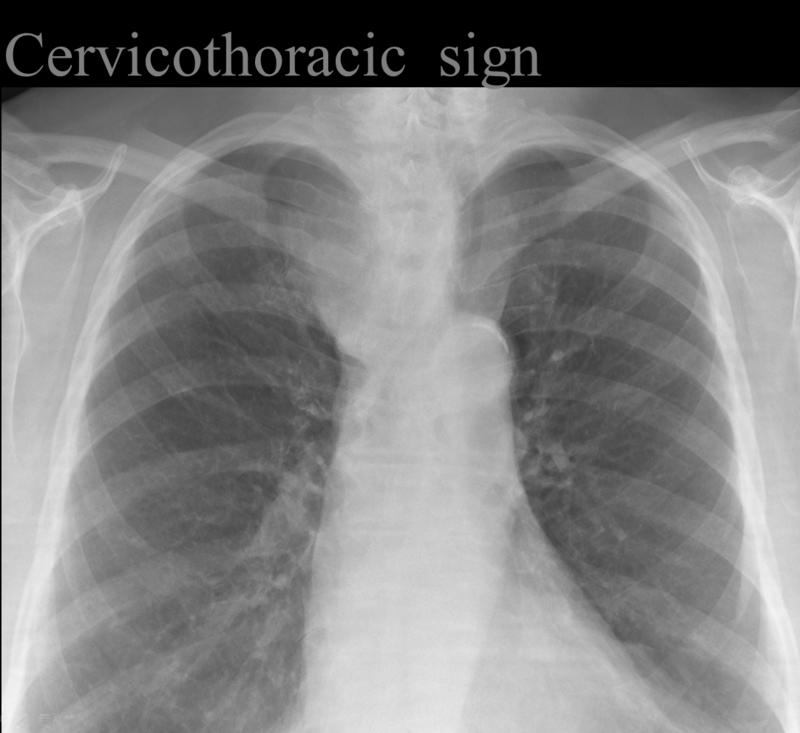

Gallery Signs Cervicothoracic sign (Thyroid mass- see next image)

Cervicothoracic sign

(Thyroid mass- see next image)